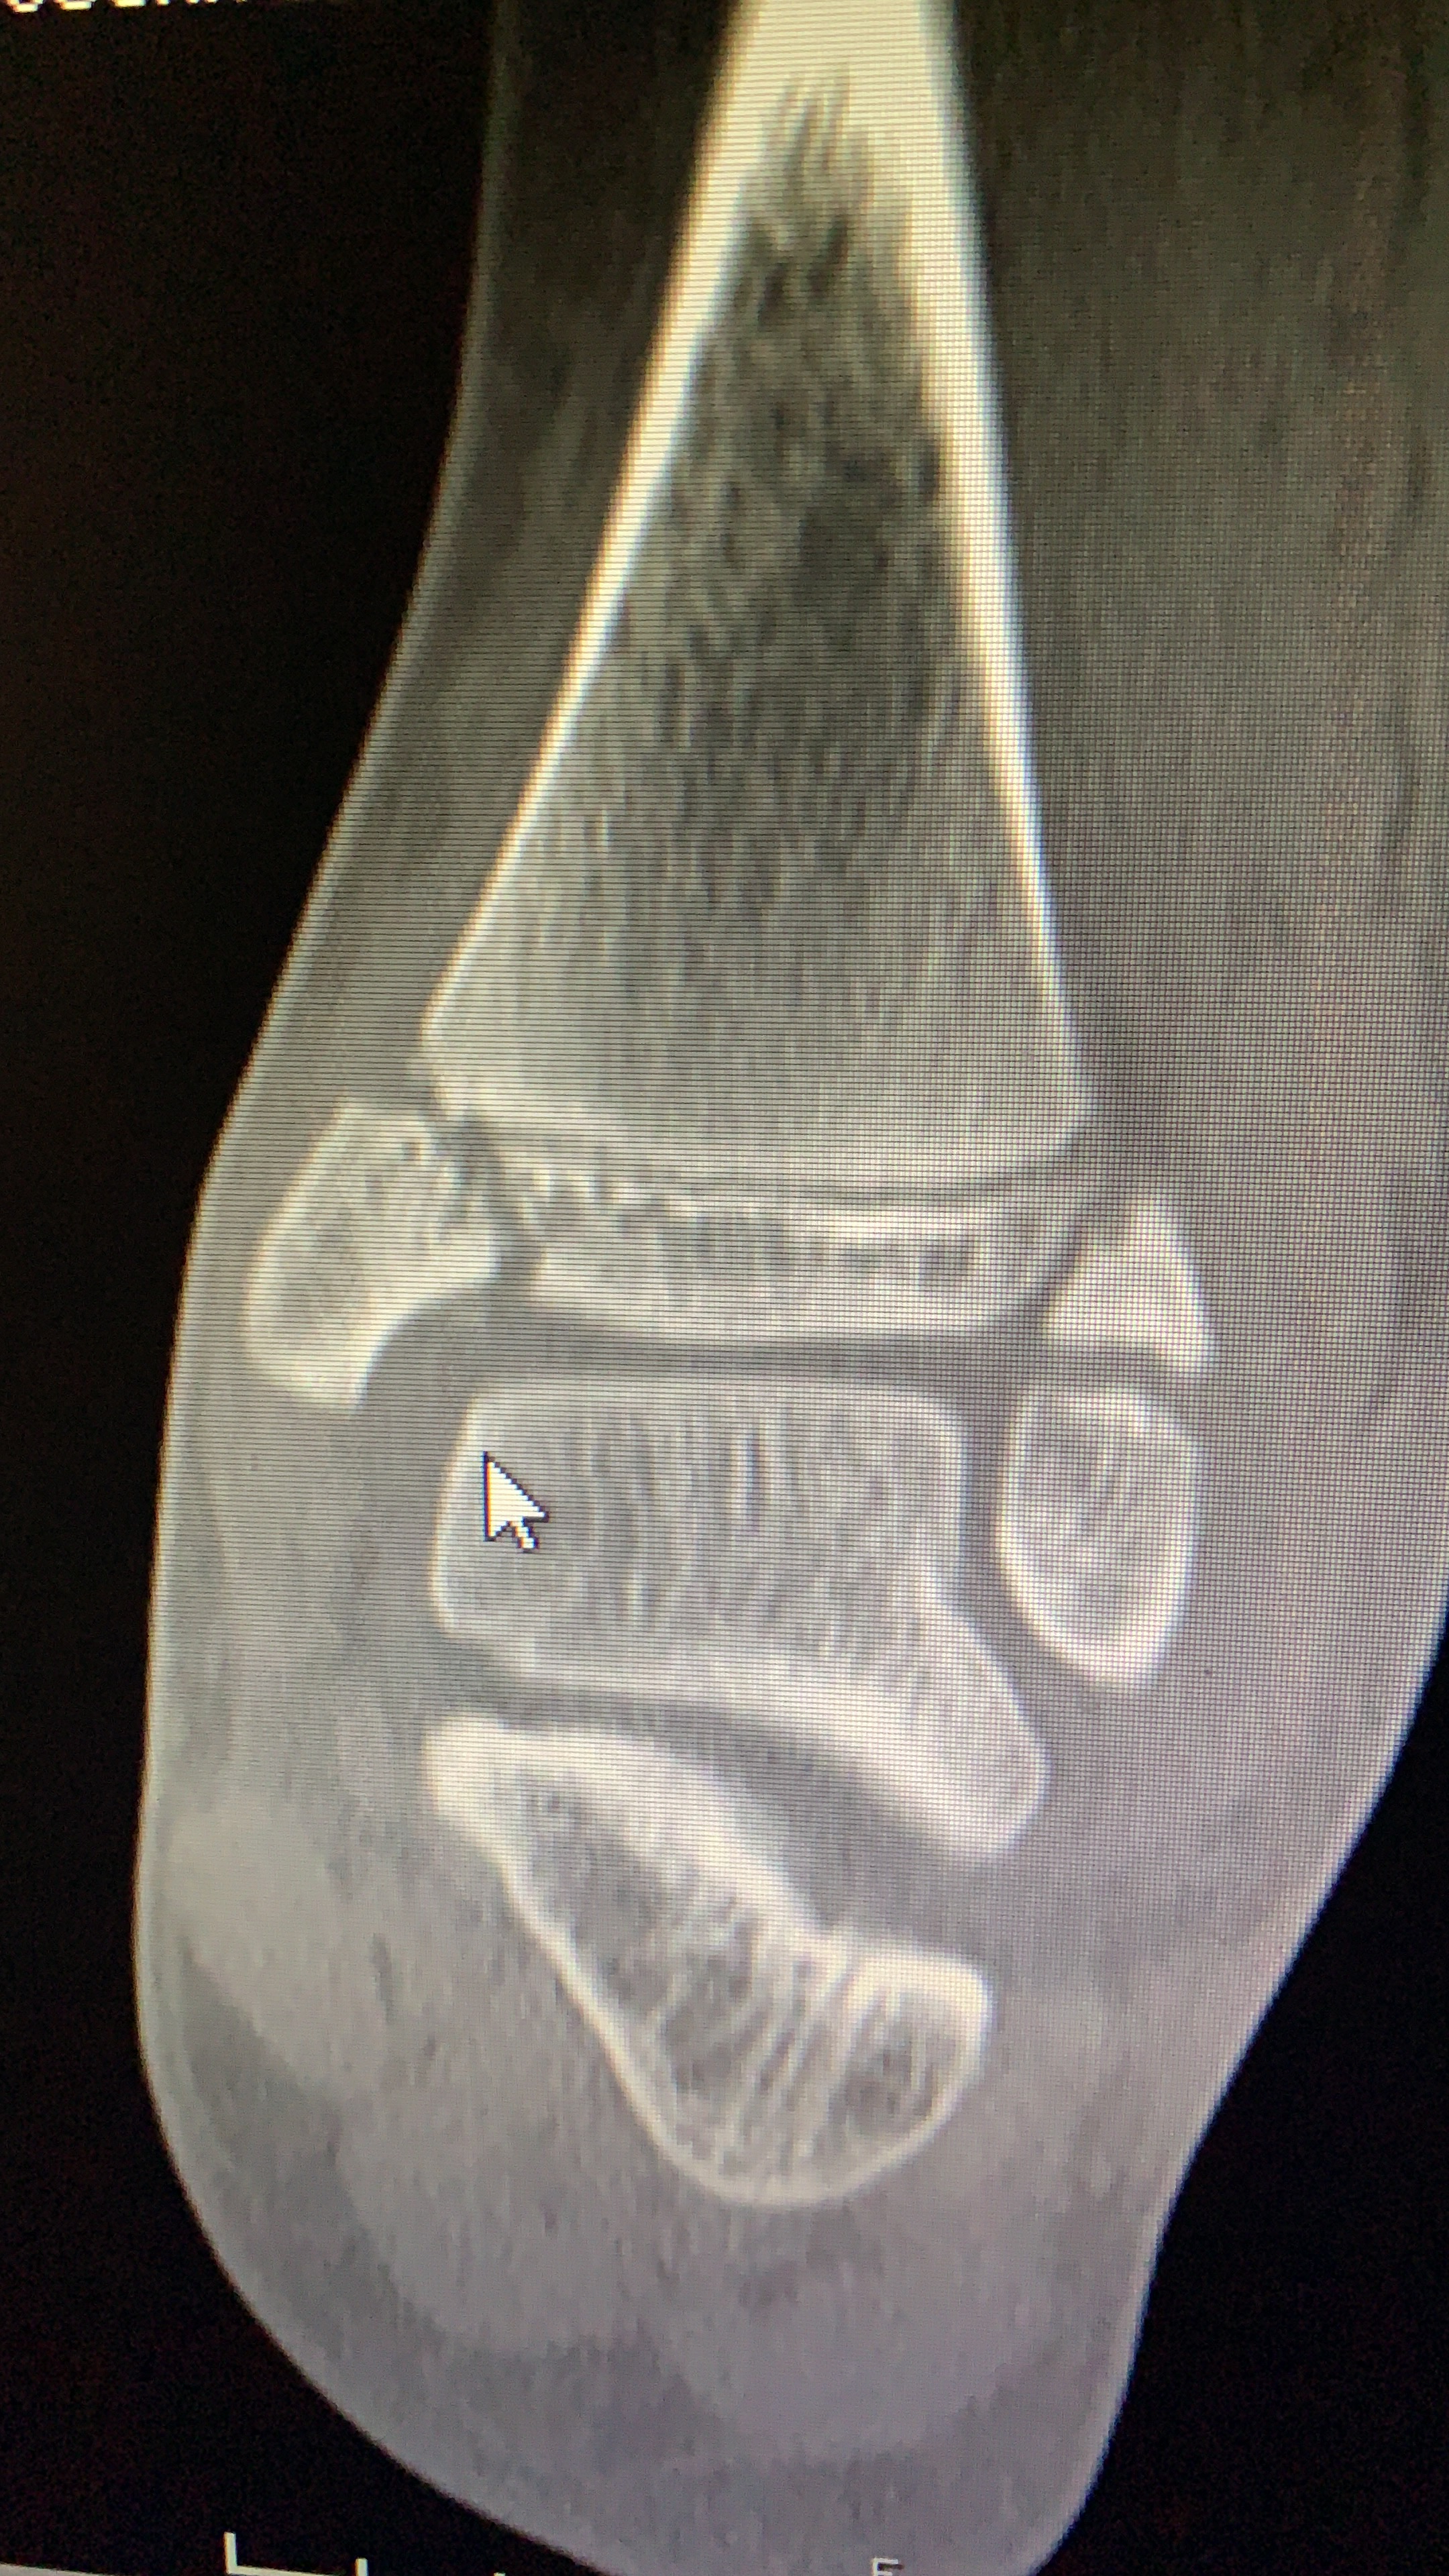

Galería de fotos clínica, servicios, cirugías, casos de pacientes Visítenos, ambiente limpio, agradable y seguro. Trabajando Operando en tiempos de coronavirus Dr Barquero Traumatologo Compartir en X (Se abre en una ventana nueva) X Comparte en Facebook (Se abre en una ventana nueva) Facebook Imprimir (Se abre en una ventana nueva) Imprimir Compartir en WhatsApp (Se abre en una ventana nueva) WhatsApp Enviar un enlace a un amigo por correo electrónico (Se abre en una ventana nueva) Correo electrónico Me gusta Cargando...